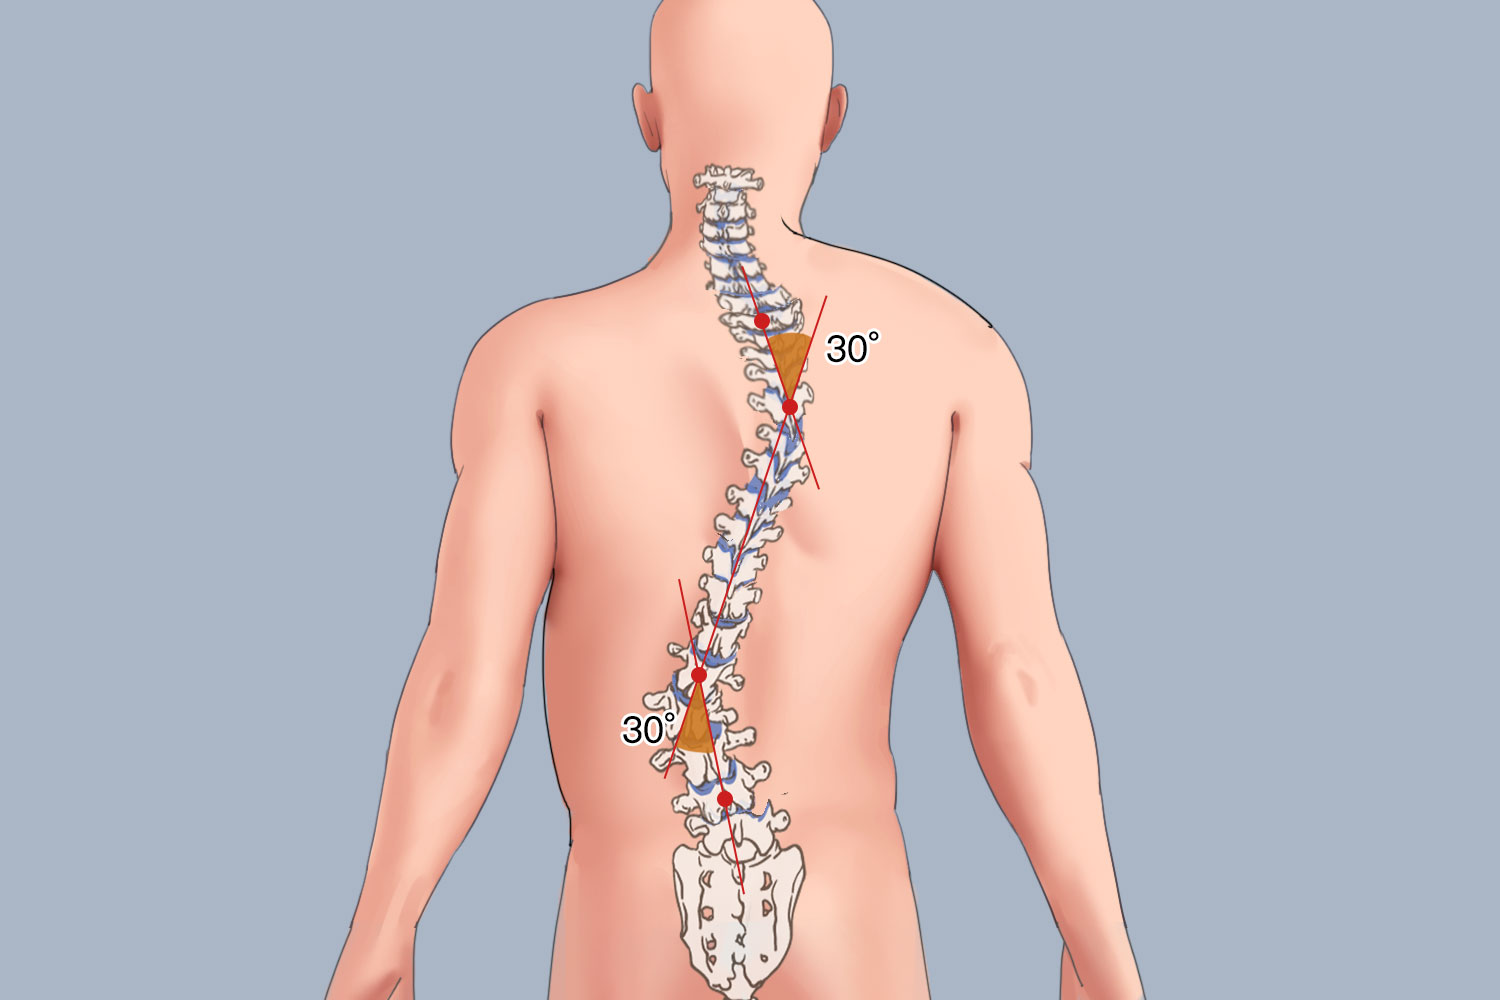

Zhengzhou Zhenshan Medical Equipment Co., Ltd. was formally established in 2017. The company specializes in R&D, production and sales of rehabilitation aids and consumables, including orthoses, low-temperature thermoplastic sheets and orthopedic insoles. The company has a strong R&D team, a professional marketing team and a perfect after-sales service system. The products are mainly exported to Europe, Southeast Asia, the Middle East, Africa and many other countries."People-oriented, scientific spirit, win-win cooperation, continuous learning" is our company's corporate values. We will do our best to serve every customer, produce better products, and make due contributions to the medical device industry! We look forward to cooperating with you to create a brilliant future!